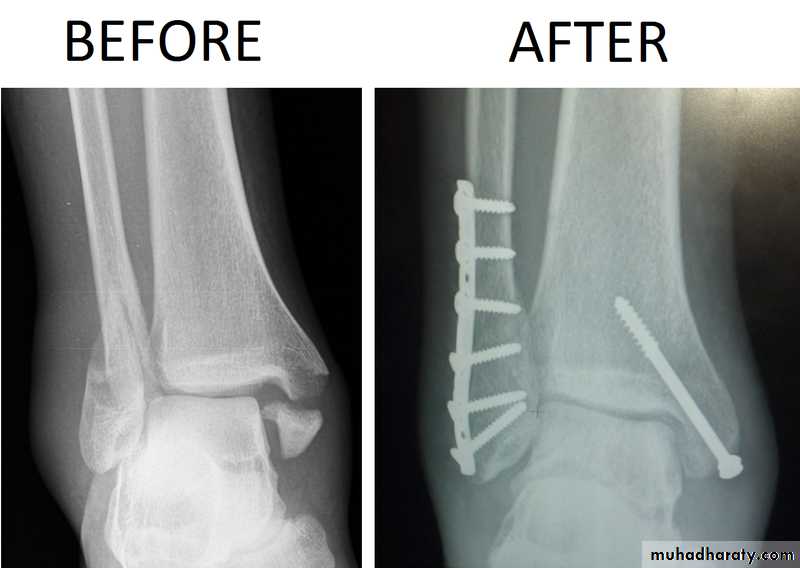

For displaced fractures and failed conservative treatment, open reduction and internal fixation is mandatory by malleolar screws, plate and screws.

Fractures ankle

X ray: it is essential to do anteroposterior, lateral and mortise views (The AP mortise view is done with the leg internally rotated 15-20o ,This view permits examination of the articular space (clear space). The width of the clear space between the talus and the articular surfaces of the medial malleolus, the tibial plafond and the lateral malleolus should be equal.

X- ray shows the type of fractures, Any shift, tilt or displacement in talus is serious, If the fibular fractures above the tibiofibular joint there must be a diastasis.

Reduction should be anatomical and accurate since this is a joint fracture, in order to prevent post traumatic osteoarthritis.